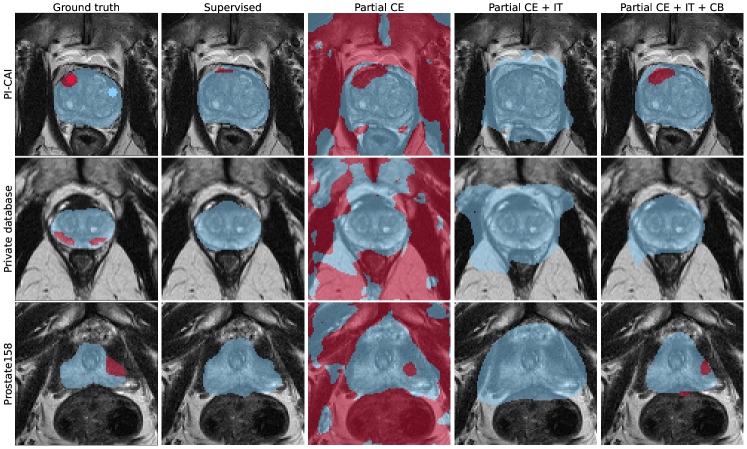

Figure 1 shows performance of all considered models for the three metrics of interest, namely sensitivity at 1 FP, AP and AUROC. Figure 3 provides examples of visual results of lesion detection maps for some 3D models. Extended visual results, including of 2D and ensemble models, are showcased in Appendix E.

Our proposed weakly supervised method achieves competitive results compared to fully supervised baselines, while requiring only 14% of annotation voxels of clinically significant lesions. It consistently outperforms 2D supervised DynUNet trained with cross-entropy and generalized DICE loss. In the 3D configuration, the model trained with full segmentation annotations remains better overall. The addition of the more precise common bounds (CB) size constraint gives better results compared to the image tag (IT) model that was proposed in [Duran et al.(2022)Duran, Dussert, and Lartizien].